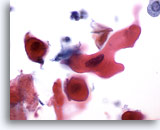

画像 3:肺FNA、肺大細胞癌 腫瘍細胞は、このシート内に見られる数個のアポトーシス細胞より大型です。細胞質の保存状態は良好であり、量が中程度で密度が高く、微細な空胞化が見られます。扁平上皮への分化の特徴である細胞間橋を思わせる細胞変化が局所的に見られます。核は円形から卵円形を呈し、結合性が疎のクロマチン集塊および肥厚化した滑面核膜が認められます。核小体は目立ち、不整形を呈し、単個から複数個見られます。高いN/C比を示します。

60倍

画像 3

肺FNA、肺大細胞癌

腫瘍細胞は、このシート内に見られる数個のアポトーシス細胞より大型です。細胞質の保存状態は良好であり、量が中程度で密度が高く、微細な空胞化が見られます。扁平上皮への分化の特徴である細胞間橋を思わせる細胞変化が局所的に見られます。核は円形から卵円形を呈し、結合性が疎のクロマチン集塊および肥厚化した滑面核膜が認められます。核小体は目立ち、不整形を呈し、単個から複数個見られます。高いN/C比を示します。

60倍